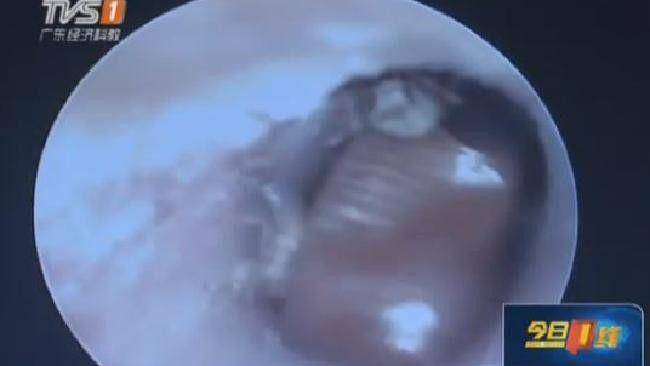

Dikutip dari Mirror.co.uk, ia pergi ke rumah sakit setelah merasakan sakit dan gatal di dalam telinganya. Saat dicek, sang dokter terkejut karena melihat binatang merayap dengan serangga kecil di sekitarnya. Total ada 1 kecoak dewasa dan 25 kecoak anak yang bersarang di telinga Li.

Dokter meyakini jika itu adalah kecoak betina yang masuk ke dalam telinga Li sebelum akhirnya bertelur. "Kami melihat benda seperti serangga yang menghalangi saluran telinga secara penuh," tutur sang dokter, Yang Jing.